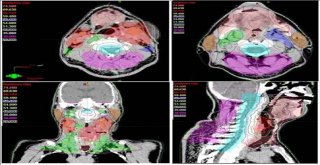

Kanser Tedavisinde Yapay Zeka Başarısı